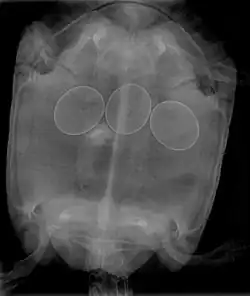

In reptiles, it is inadvisable to attempt to break a reptile egg to remove it from an egg-bound female. This procedure may be done by a veterinarian, who will insert a needle into the egg, and withdraw the contents with a syringe, allowing the egg to collapse and be removed. Non-surgical interventions include administering oxytocin to improve contractions and allow the egg(s) to pass normally. In many cases, egg-bound reptiles must undergo surgery to have stuck eggs removed.

Egg binding in reptiles is quickly fatal if left untreated; therefore, gravid females who become very lethargic and cease feeding need immediate medical treatment in order to treat the potentially life-threatening condition.

Egg binding can occur if an egg is malformed and/or too large, the animal is weakened by illness, improper husbandry, stress, or if hormonal balances are wrong (producing weak contractions). Factors that can contribute to the risk of egg binding include calcium deficiency, breeding animals that are too young or too small, not providing suitable laying areas (leading to deliberate retention of eggs), and overfeeding of species in which clutch size is dependent on food intake, such as the veiled chameleon.[3]